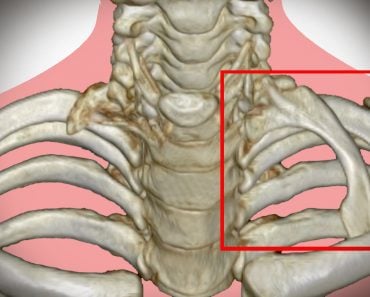

The vertebral column picks up from where the skull ends and goes right down to the lower back. It is composed of 31 individual bones called vertebrae, and the entire column is divided into 5 sections – cervical, thoracic, lumbar, sacrum and coccyx – in descending order of location. Each section has a different number of vertebrae, interspersed with intervertebral discs. These discs allow for movement, act as shock absorbers, form fibrocartilaginous joints, etc. They are an important part of the vertebral column.

The typical structure of a vertebra is illustrated below:

There is a part of the body, the vertebral foramen, where the spinal cord, the process that handles nerves from the brain, passes through. Several other processes exist in the vertebral bone, such as the spinous process, seen in the picture above. These processes are elongated, bony protrusions that help in association and articulation with muscles and other bones.

There are 12 thoracic vertebral bones, referred to as T1 – T12.

When you think of the thoracic region, the first thing that comes to mind is the rib cage. The rib cage lies in the thoracic region of the body, and the thoracic vertebrae have a slight modification in order to articulate with the ribs. This modification comes in the forms of demifacets. Facets are basically flattened surfaces of a bone. A demifacet is half of a facet, and is meant for articulation with the ribs and coastal cartilage. The vertebrae have both superior and inferior demifacets. Each rib articulates with the corresponding vertebra and the vertebra above it.